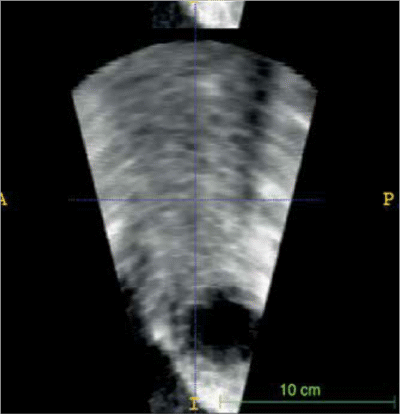

Zamknięcie przecieków zastawkowych metodą przezskórną stanowi duże wyzwanie kliniczne, szczególnie ze względu na złożoność anatomiczną kanałów PVL (ang. paravalvular leak – przecieków zastawkowych) oraz ryzyko kolizji okludera z mechanicznymi elementami zastawki. Zespół badawczy postawił sobie za cel ocenę możliwości wykorzystania danych z echokardiografii przezprzełykowej (3D-TEE) do stworzenia modeli 3D, które pozwoliłyby lepiej dobrać typ i rozmiar okludera przed zabiegiem.

Zespół z GCM i ŚUM wykorzystał dane z echokardiografii 3D-TEE, które po konwersji do plików 3D, dzięki segmentacji w oprogramowaniu powiązanym z drukarką 3D (slicer), zostały wydrukowane w rzeczywistej skali na drukarce Stratasys Objet 30 (v.3) w technologii PolyJet.

W projekcie przeanalizowano 8 przypadków pacjentów z PVL w mitralnych zastawkach mechanicznych lub biologicznych. W testach symulacyjnych przeprowadzonych na wydrukowanych modelach, dobrano optymalne rozmiary okluderów, co później porównano z rzeczywistym postępowaniem klinicznym.